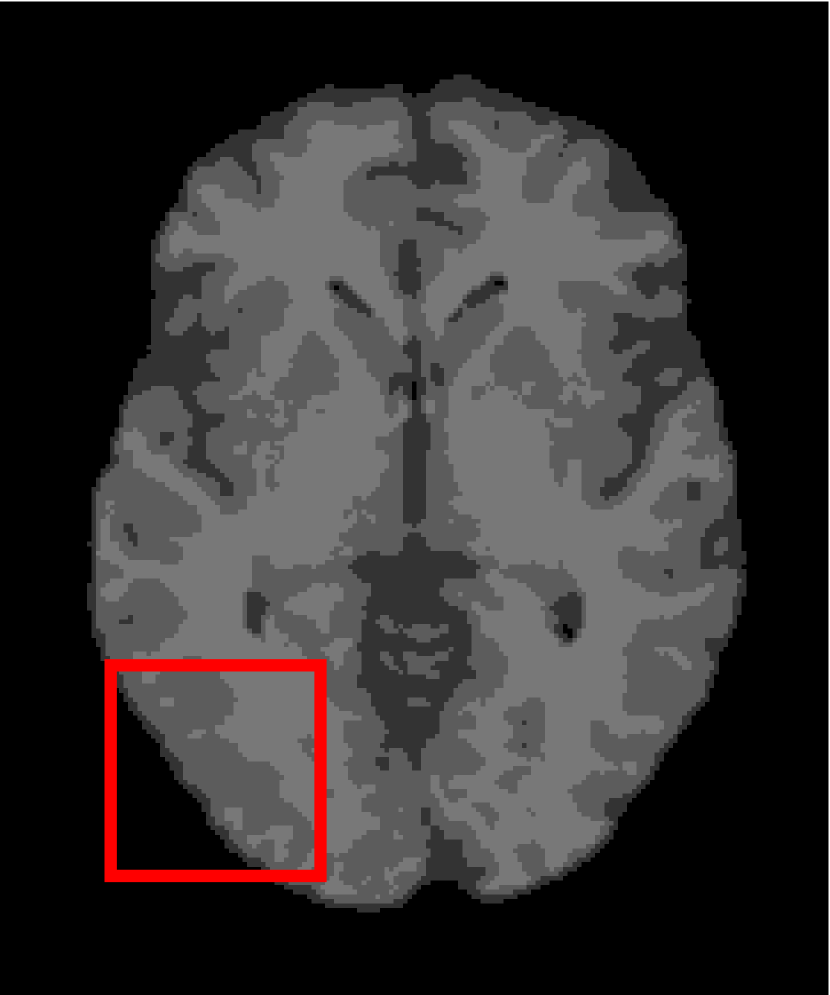

4.4.2 Results on Medical Images

Next, we representatively segment five medical images from BrianWeb. They are represented as five slices in the axial plane with a sequence of 70, 80, 90, 100 and 110, which are generated by T1 modality with slice thickness of 1mm resolution, 9% noise and 20% intensity non-uniformity. Here, we set c=4𝑐4c=4 for all cases. The comparison between WRFCM and its peers are shown in Fig. 9 and Table II. The best values are in bold.

Figure 9: Segmentation results on five medical images. The parameter: ϕ=5.35italic-ϕ5.35\phi=5.35. From top to bottom: noisy images, ground truth, and results of FCM_S1, FCM_S2, FLICM, KWFLICM, FRFCM, WFCM, DSFCM_N, and WRFCM.

By a view of the marked red square in Fig. 9, we find that FCM_S1, FCM_S2, FLICM, KWFLICM and DSFCM_N are vulnerable to noise and intensity non-uniformity. They give rise to the change of topological shapes to some extent. Unlike them, FRFCM and WFCM achieve sufficient noise removal. However, they produce overly smooth contours. Compared with its seven peers, WRFCM can not only suppress noise adequately but also acquire accurate contours. Moreover, it yields the visual result closer to ground truth than its peers. As Table II shows, WRFCM obtains optimal SA, SDS and MCC results for all five medical images. As a conclusion, it outperforms its peers visually and quantitatively.